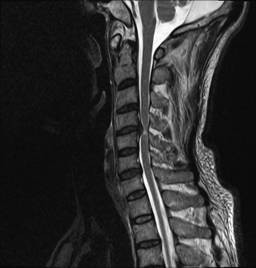

中年男性41岁,因“行走不便2年,加重伴双手麻木2周”之主诉入院,症状主要为:颈部疼痛、僵硬,双下肢无力、行走不稳,双手麻木,协调性差,右手握笔困难。入院查体:步态不稳,C3-C7压痛、叩击痛,肢痛温觉减退,双上肢肢肌力5-级,双下肢肌力4-级,肌张力增高,双下肢腱反射亢进,病理征(+),行颈前路小切口突出椎间盘切除、前路颈椎桥形锁定植骨融合(ROI-C假体),无需前路钢板,术后四肢麻木明显缓解,右上肢精细动作明确增强,可写字,行走不稳消失,肌力基本正常,颈部活动度无明显受限。(图1、图2)

图1:术前颈椎MRI提示颈椎退行性变,C4/5椎间盘突出、脊髓出现高信号改变,C4硬膜囊受压变形。